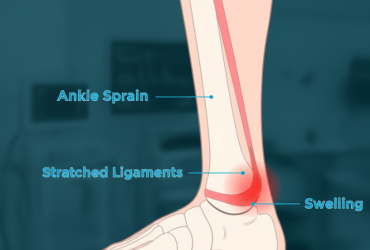

Ankle Sprains – stretching or tearing of ligaments around the ankle, one of the most common foot injuries.

Ankle Sprains

An ankle sprain is an injury where ligaments are stretched or torn, usually from twisting, falling, or sports. It causes...